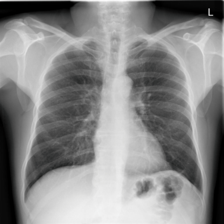

4.7.2 Activation Response Maps

As shown in Fig. 9, given the text lungs, we can find that the activation maps can accurately highlight the target regions. Therefore, we can achieve a higher performance on the downstream tasks. However, the activation maps are imperfect, as the background regions are also highlighted.